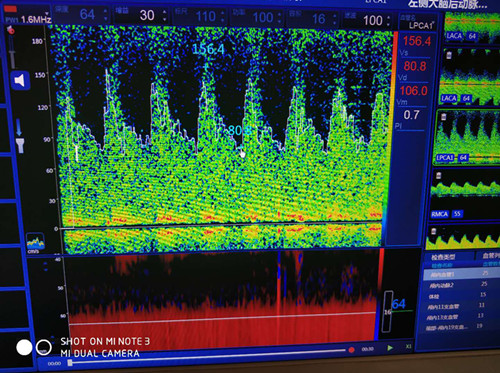

近日,一名中年女性在我院功能科進(jìn)行經(jīng)顱多普勒(TCD)體檢時(shí),主檢醫(yī)師發(fā)現(xiàn)該女性后循環(huán)動(dòng)脈血流速度異常增高,前循環(huán)動(dòng)脈呈相對(duì)低波動(dòng)改變,雙側(cè)壓頸試驗(yàn)陰性。這種異常的顱內(nèi)動(dòng)脈改變引起了主檢醫(yī)師的關(guān)注,遂請(qǐng)科里高年資醫(yī)師進(jìn)行進(jìn)一步詳細(xì)檢查。經(jīng)過(guò)詢問(wèn)病史,并結(jié)合TCD檢查結(jié)果和頸動(dòng)脈超聲觀察,最終診斷為煙霧病。

大腦后動(dòng)脈血流速度增高